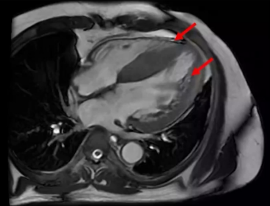

2) 病情发展与处理:利尿治疗后水肿消退不明显,因右侧胸腔积液严重,进行胸腔穿刺引流,引流出2800 ml胸水,胸水性质倾向于漏出液,未发现肿瘤细胞及结核细胞。继续药物治疗后,复查胸部CT提示胸水减少,仍有少量胸腔及心包积液,患者未完全转复,仅心室率得到控制70-90次/分。为明确心衰病因,进行冠脉造影,未发现明显冠脉狭窄,后行心脏核磁检查,发现左室各壁及室间隔增厚,全心运动减低,左心功能不全,左心室各壁心肌增厚,伴有多发斑片状延迟强化。

·心肌淀粉样变性:另一种可引起心肌肥厚和心衰的疾病。团队注意到患者心脏CMR存在“多发斑片状延迟强化”,这是一个需要警惕的信号。虽然患者缺乏典型心电图低电压等表现,且心功能随治疗改善,但仍建议在半年至一年后复查CMR,必要时进行心内膜心肌活检以完全排除。这体现了严谨的临床思维。